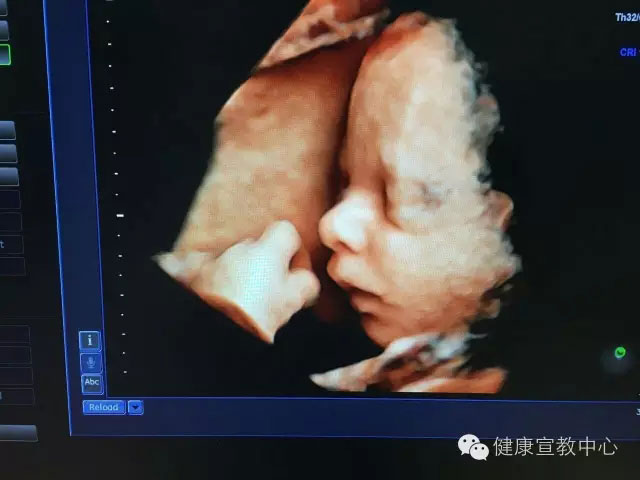

(胎兒顏面部3維成像技術(shù))